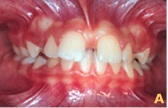

Caso 2

Quando se distende o freio labial e, como conseqüência desta manobra, surge uma área isquêmica na região da papila incisiva, deve-se suspeitar do envolvimento do freio, em caso de diastema inter-incisal.

Ainda o caso 1

Já os casos patológicos, com disturbios imediatos e de certa gravidade, exigem intervenção imediata do profissional, independente do estágio de desenvolvimento do paciente.

Neste contexto, considera-se a divergência do longo eixo das coroas dos incisivos centrais, problemas periodontais decorrentes da impacção alimentar, dificuldade de higienização, a estética e o desenvolvimento de hábitos bucais deletérios como quesitos que mereciam atenção imediata.